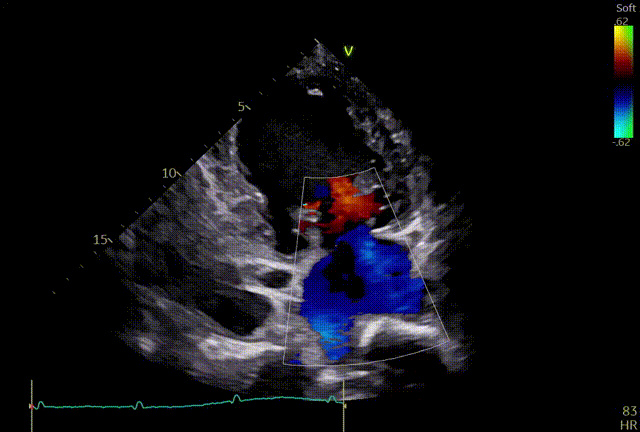

术前心超团队王蓓教授以及余婵教授对患者的瓣膜解剖情况进行了详细的评估:

① 二尖瓣后叶广泛栓系,前后叶对合不良,二尖瓣重度关闭不全,Carpentier分型Ⅲb,反流程度4+;

② 画迹法显示二尖瓣瓣口面积5.25cm²,平均跨瓣压差4.2mmHg;

③ 二尖瓣前叶(A1)长度28.5mm,二尖瓣后叶(P1)长度: 10.4mm;二尖瓣前叶(A2)长度28.4mm,二尖瓣后叶(P2)长度: 12.7mm二尖瓣前叶(A3)长度22.6mm,二尖瓣后叶(P3)长度: 11.5mm;

④ 3区前后叶对合gap 4.5mm,2区前后叶对合gap 3mm。

术前TEE及左房压

1区

1区带彩

2区

2区带彩

3区

3区带彩

3D

3D带彩